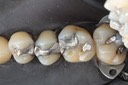

Mark Chun #14 finish

Mark Chun #14 buccal view